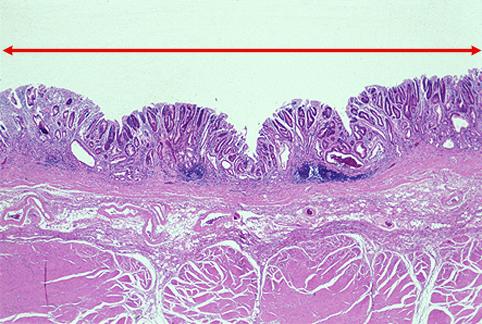

clasificación del pacienteTumor Epitelial Maligno/Adenocarcinoma

parte(separada por órganos)estómago(región)/ángulo

método de exámenMicro

clasificación ectoscópica de tumoresTipo 0(tipo superficial)/Tipo IIc(IIc)

diámetro mayor del tumor25 - 29

grado de penetraciónm